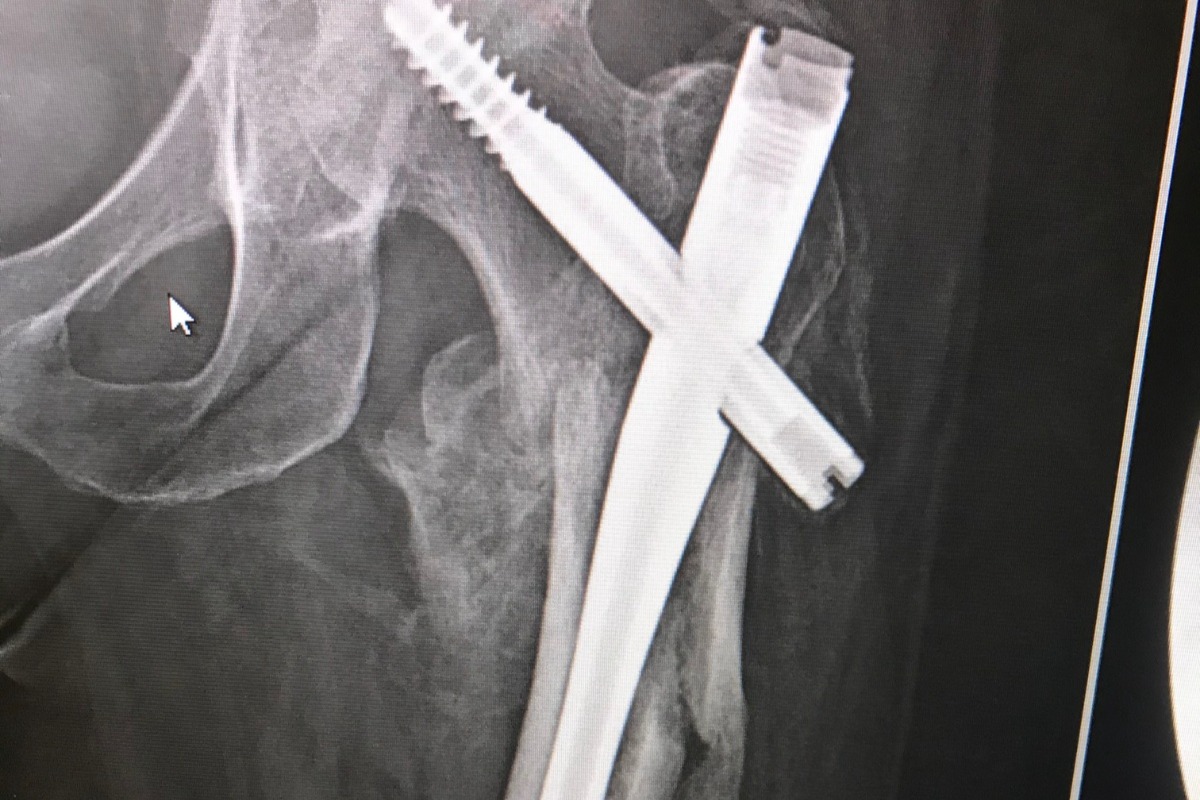

Many thanks to everyone that has donated. Carrie is now recovering from a 3rd emergency surgery. Last surgery in June, they replaced the hardware from last year and also had to replace her hip. The recent hip replacement was not fitting and popped out of the socket. She went to the doctor and it took multiple tries to shove it back in place. Then it dislocated again. When she went back to the doctor, they had to perform emergency surgery in July to replace the hip replacement. Below is a pic after the latest 3rd surgery.